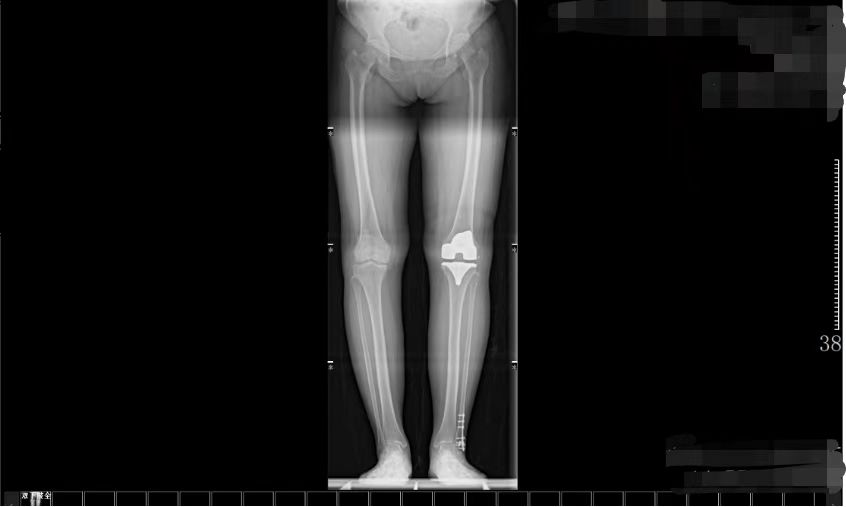

经胡舒主任详细检查与评估,冯阿姨被诊断为重度膝关节骨性关节炎。由于保守治疗效果不佳,为彻底解决疼痛、恢复关节功能,胡主任建议进行膝关节置换术。在充分沟通和了解了自己的疾病及治疗方式后,冯阿姨选择在家门口的东凤人民医院手术治疗。

(术前) (术后)